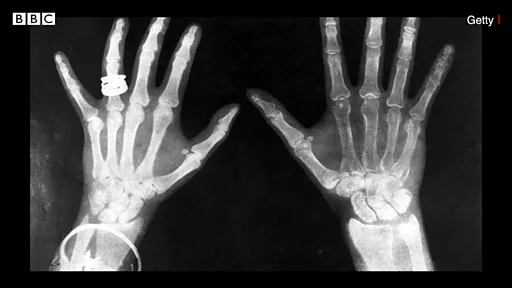

• नाख़ूनों का ख़राब होना